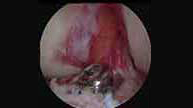

Si la fractura está desplazada el tratamiento es quirúrgico. El método tradicional consiste en cirugía abierta, con una importante cicatriz y un postoperatorio muy doloroso. Nosotros realizamos la reparación con artroscopia obteniendo un mejor resultado estético y un postoperatorio más confortable iniciando la rehabilitación de inmediato. Además el daño a la articulación es menor permitiendo una mejor recuperación del paciente.

Visión artroscópica de reparación de fracturas y fijación con tornillos